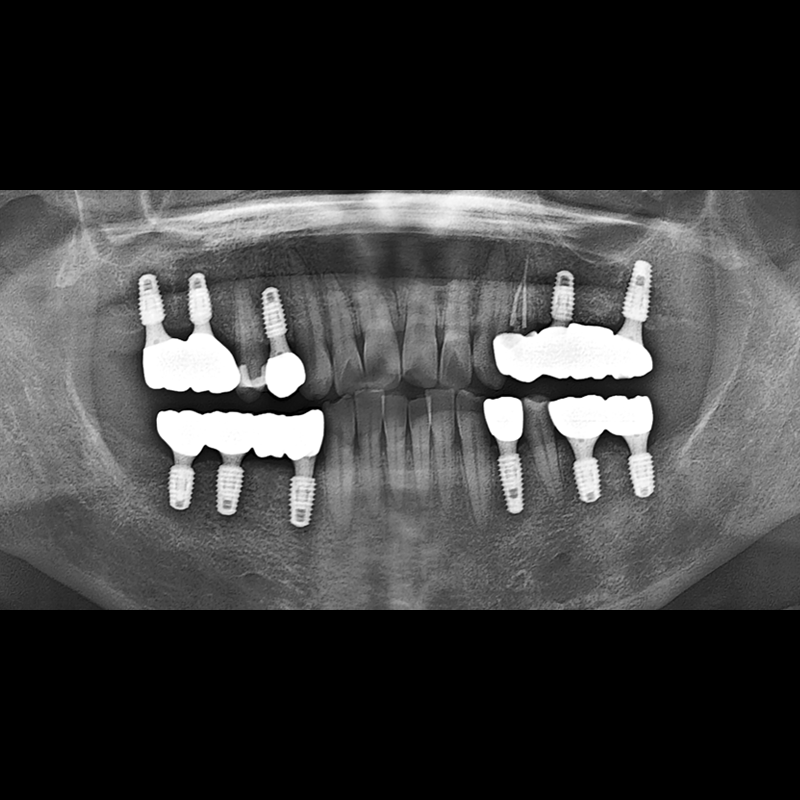

BEFORE AFTER

种植牙前后的照片 2025.12.10

在缺失的牙齿部分和难以挽救的牙齿位置植入了种植牙。